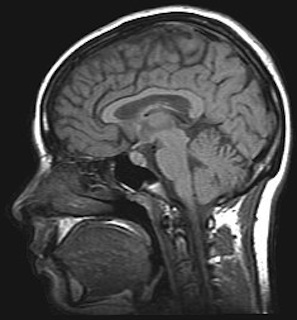

Option A: Neurobiology & behaviour (15 / 25 hrs)

The core topics are neural development, the human brain and perception of stimuli.

The additional HL topics are innate and learned behaviour, neuropharmacology, and ethology.

Option A - Neurobiology - Activities for learning

The ideas for learning activities on this page cover the IB guide for this topic. There is a mix of laboratory work, theory...